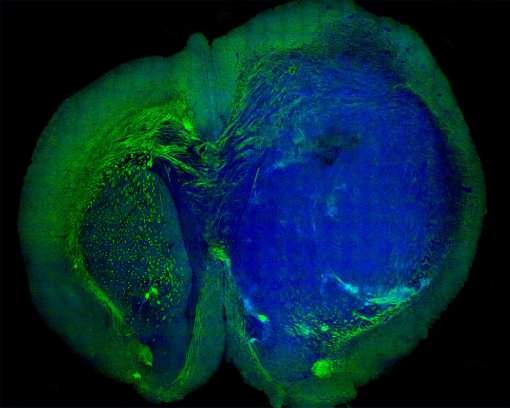

A nova tecnologia é baseada em uma espécie de microscopia a laser, que analisa o tecido ao nível microscópico, gerando uma imagem que mostra ao cirurgião até onde vai o tumor.

Agora, o grupo está trabalhando para desenvolver a técnica, chamada microscopia SRS, para um ensaio clínico em humanos - os testes foram feitos em culturas celulares e no cérebro de cobaias.

"Nós precisamos de melhores ferramentas para visualização dos tumores durante a cirurgia, e a microscopia SRS é altamente promissora," disse o Dr. Daniel Orringer, membro da equipe. "Com a SRS podemos ver algo que é invisível ao microscópio cirúrgico convencional."